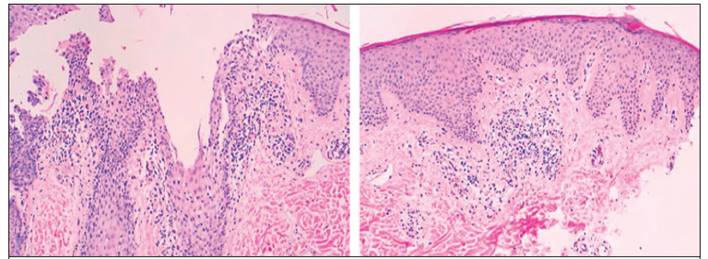

En 2017 consulta por aparición de placas eritematosas ovaladas con pápulas centrofoliculares en espalda, lesiones de 1 año de evolución. Presenta al menos 6 lesiones muy sugestivas de linfoma cutáneo de células T tipo micosis fungoide vs. pitiriasis rubra pilaris. Se tomó biopsia a nivel particular, sin embargo, el día de la cita el reporte histológico se encontraba pendiente. Un mes después, en la próxima cita, se valoran biopsias cutáneas, las cuales mostraron engrosamiento irregular de epidermis con escasa espongiosis focal, paraqueratosis alternante, infiltrado inflamatorio linfocítico alrededor de folículos y tapones de queratina.13-14 El diagnóstico patológico fue compatible con pitiriasis rubra pilaris tipo IV.7 Inicialmente, se trató mediante terapia tópica con betametasona y fototerapia, por 2 meses (dosis acumulada 6000mJ).

Para este paciente en un inicio se planteó como diagnóstico diferencial linfoma cutáneo de células T tipo micosis fungoide (LCCT) versus pitiriasis rubra pilaris, debido a la presencia de máculas pigmentadas que pueden apreciarse en la PRP y en el LCCT, en su estadio macular. Pese a esto, la biopsia demostró el diagnóstico definitivo de PRP tipo IV. Al ser un paciente con VIH, podría haberse planteado la posibilidad de que se tratase de una PRP tipo VI, aunque no presentaba acné conglobata, liquen espinuloso o hidradenitis,11 para asociarlo con dicha clasificación.